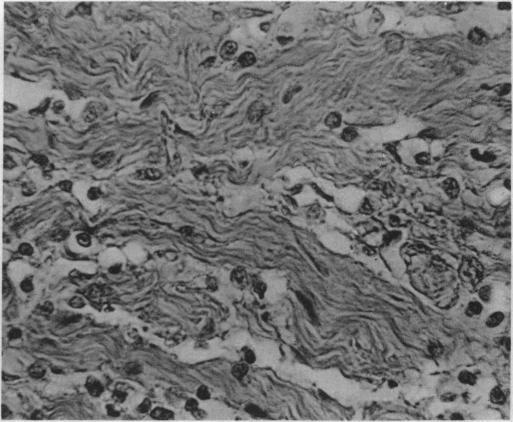

Teratoma of testis; spontaneous disappearance of lung metastases.

Teratoma of testis.

[Atrophy and scar tissue formation in teratoids of the testes with generalized malignant metastases].